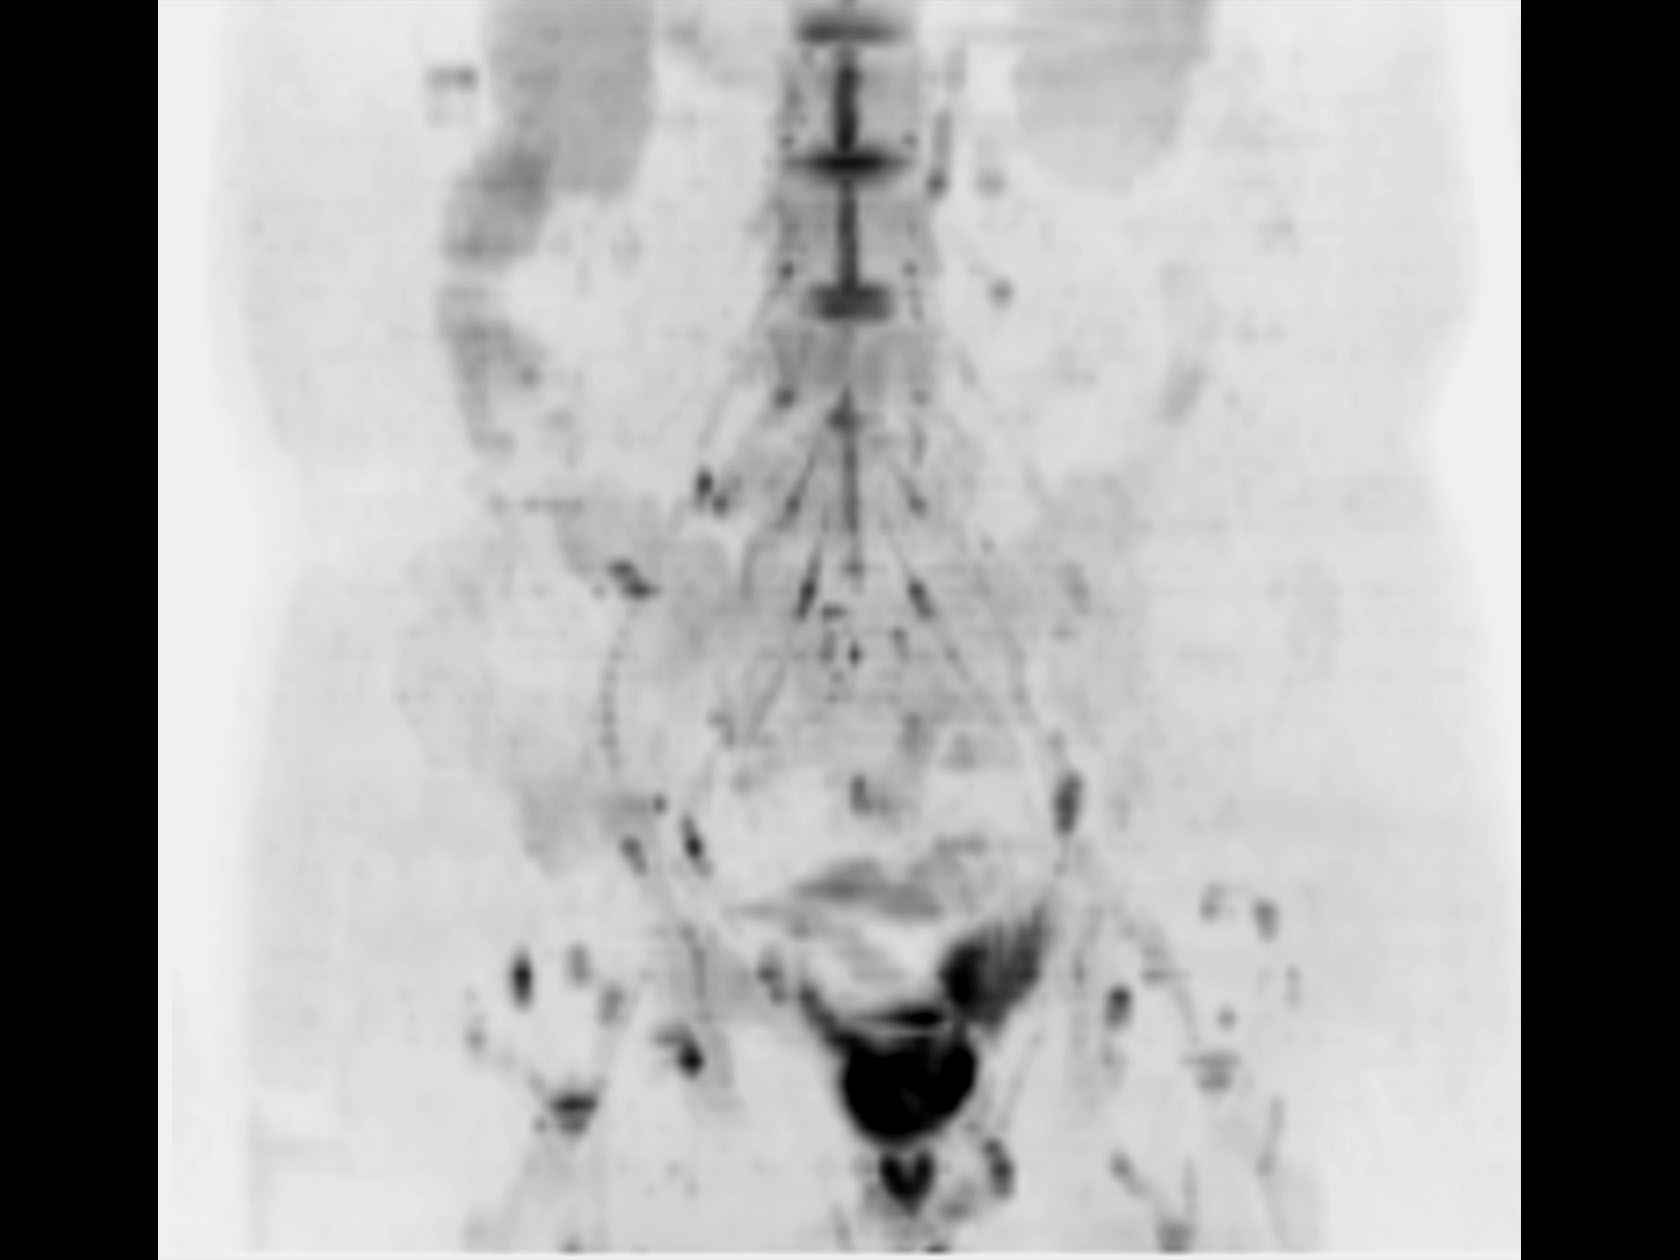

DWIBS (MIP)